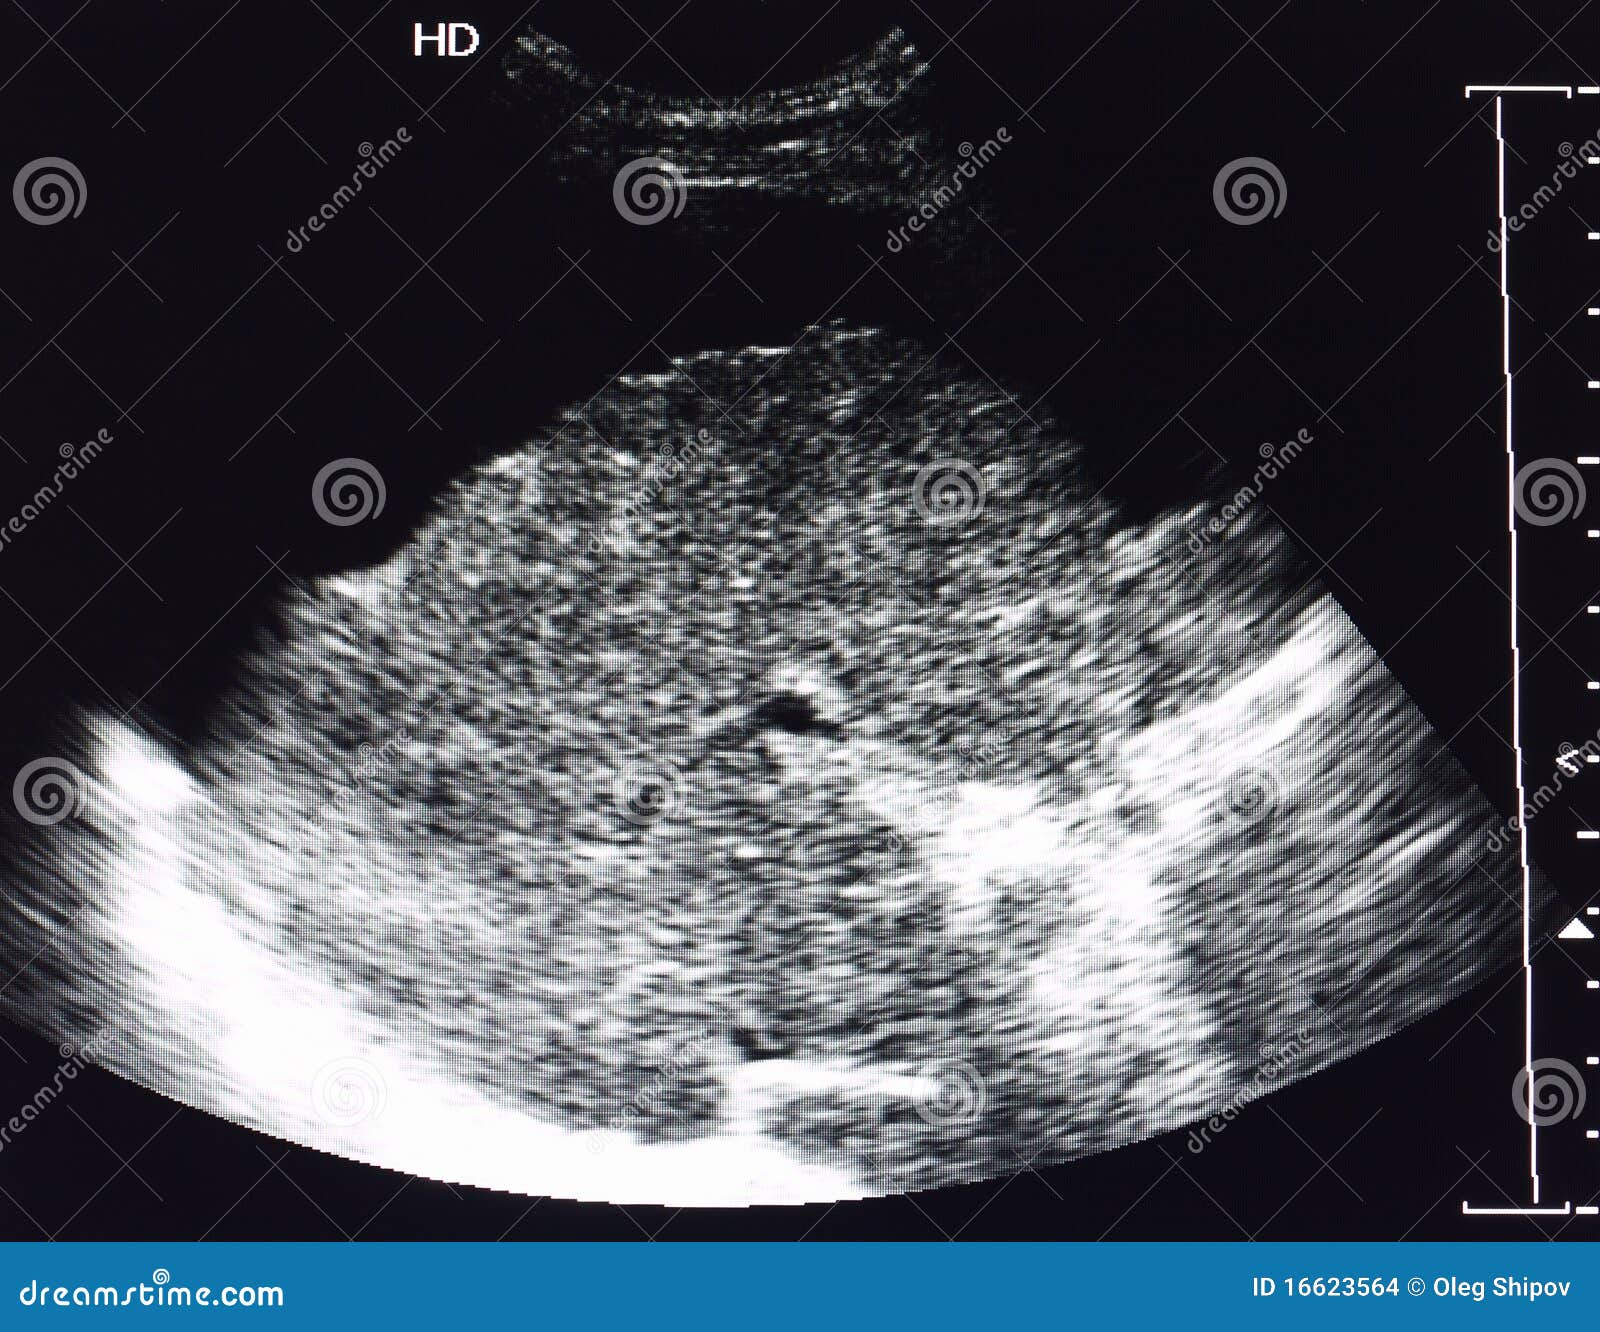

Normal ultrasound liver pattern. Echogenicity and echodensity of the …

ultrasound scan showing increased echotexture of the liver in …

Ultrasound Image of Liver Cirrhosis Stock Photo – Image of healthcare …